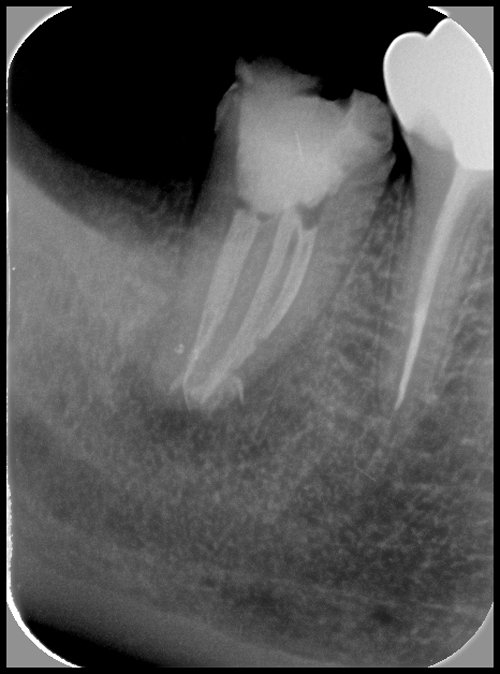

MICROCHIRURGIE ENDODONTIQUE

La microchirurgie endodontique est indiquée lorsque le retraitement endodontique est impossible.

C’est le cas quand une couronne ne peut être enlevée ou quand un retraitement n’a pas permis de résoudre l’infection.

Elle consiste à éliminer l’infection par un abord chirurgical, puis à désinfecter à nouveau la dent mais cette fois ci en passant par la racine (traitement rétrograde) et non par la couronne dentaire (traitement orthograde).

LES ETAPES DE LA RESECTION APICALE